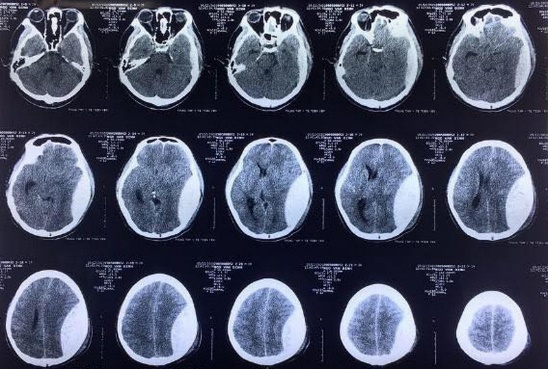

5/ Tháo nắp sọ gửi ngân hàng mô, cứu bệnh nhân chấn thương sọ não

Trung tâm Y tế Tiên Yên (Quảng Ninh) vừa tiếp nhận bệnh nhân N.V.Đ ( 29 tuổi, trú tại Đầm Hà, Quảng Ninh) bị chấn thương sọ não nặng do tai nạn giao thông. Đây là ca bệnh rất nặng, phức tạp, tình trạng người bệnh rất nguy kịch nếu chuyển tuyến bệnh nhân có thể tử vong trên đường đi do thời gian chấn thương kéo dài.

Bác sĩ trong kíp mổ đã tiến hành phẫu thuật lấy máu tụ ngoài và dưới màng cứng, cầm máu, gửi nắp sọ vào ngân hàng mô. Sau 3 giờ, ca phẫu thuật thành công. Hiện tại, bước sang ngày thứ 8 điều trị, sức khỏe bệnh nhân dần ổn định, đang được phục hồi chức năng.